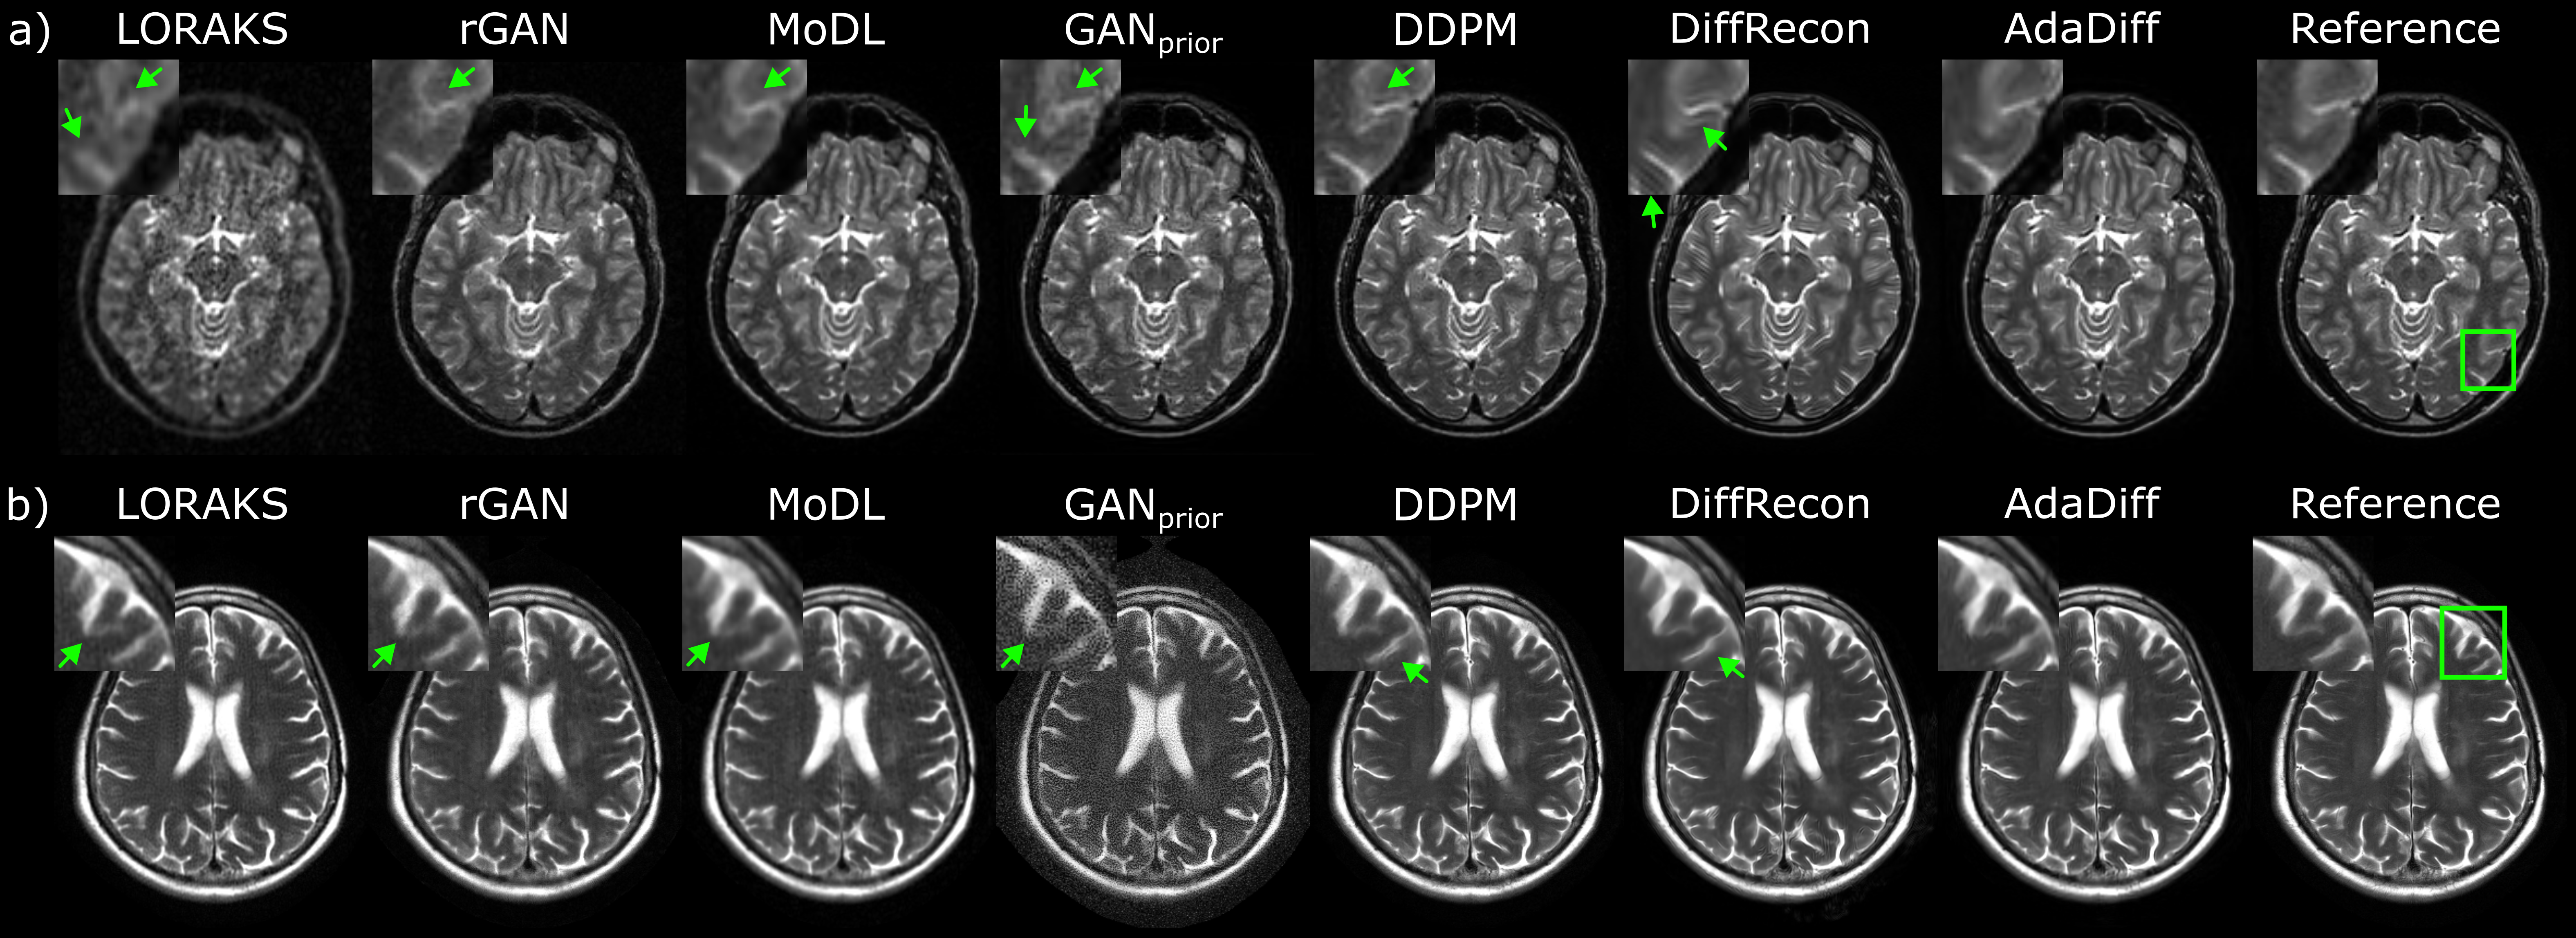

Fig. 4: Within-domain reconstructions at R=4x. Results are shown for (a) T1-weighted acquisitions in IXI, and (b) FLAIR-weighted acquisitions in fastMRI. Reconstructed images are given along with the reference image derived from fully-sampled acquisitions, and zoom-in windows and arrows are included to highlight differences among methods. LORAKS and GANprior show high noise amplification, rGAN shows residual aliasing, and MoDL shows visible spatial blurring despite high performance in quantitative metrics. Among diffusion models, DDPM has relatively higher noise and DiffRecon shows local ringing artifacts near tissue boundaries. AdaDiff produces high-quality reconstructions with lower artifacts/noise and clearer tissue depiction than competing methods.

AdaDiff was first demonstrated for within-domain reconstructions where the imaging operator and the MR image distribution were matched between the training and test sets (e.g., trained and tested for R=4x in fastMRI). Comparisons were performed against a traditional method (LORAKS), conditional models (rGAN, MoDL), an unconditional GAN that performs prior adaptation (GANprior), and unconditional diffusion models that use static priors (DDPM, DiffRecon). PSNR and SSIM for competing methods are listed in Table 1 for IXI, and in Table 2 for fastMRI. In IXI, AdaDiff achieves the highest performance among competing methods across contrasts and acceleration rates (p<<0.05), except for MoDL that performs similarly on T1 in general and on T2 at R=8x in PSNR. In fastMRI, AdaDiff again outperforms competing methods across contrasts and acceleration rates (p<<0.05), except for MoDL that performs similarly on T1, FLAIR in general, and DiffRecon that yields higher performance on T2 at R=4x and similar PSNR on T2 at R=8x. On average, AdaDiff outperforms the traditional method by 6.8dB PSNR and 15.8% SSIM, conditional models by 2.0dB PSNR and 2.5% SSIM, the adaptive GAN by 6.6dB PSNR and 15.0% SSIM, and static diffusion models by 1.3dB PSNR and 1.4% SSIM. These results indicate that the adaptive diffusion prior in AdaDiff helps improve reconstruction quality over both an adaptive GAN prior and static diffusion priors. Representative reconstructions are displayed in Fig. 4. LORAKS and GANprior show high noise amplification. While rGAN and MoDL have relatively low noise levels, rGAN shows residual reconstruction artifacts and MoDL suffers from spatial blurring, which can be attributed to its pixel-wise loss function. Among diffusion models, DDPM has relatively high noise whereas DiffRecon is effective in noise suppression via repeated averaging of multiple diffusion samples. DiffRecon tends to produce sharper images than AdaDiff likely due to its fine iteration steps, but this refinement can also introduce ringing artifacts near tissue boundaries by emphasizing high spatial frequencies. In contrast, AdaDiff adapts its diffusion prior to better conform to the distribution of test data, enabling it to produce high-quality reconstructions that clearly depict tissues with lower artifacts and noise than competing methods.